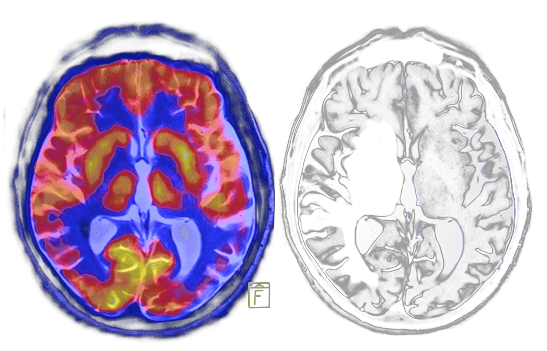

What Is Chronic Traumatic Encephalopathy (CTE)? Chronic Traumatic Encephalopathy (CTE) is a progressive degenerative brain disease caused by repeated concussions or severe blows to the head. For this reason, CTE mainly affects athletes and military veterans.